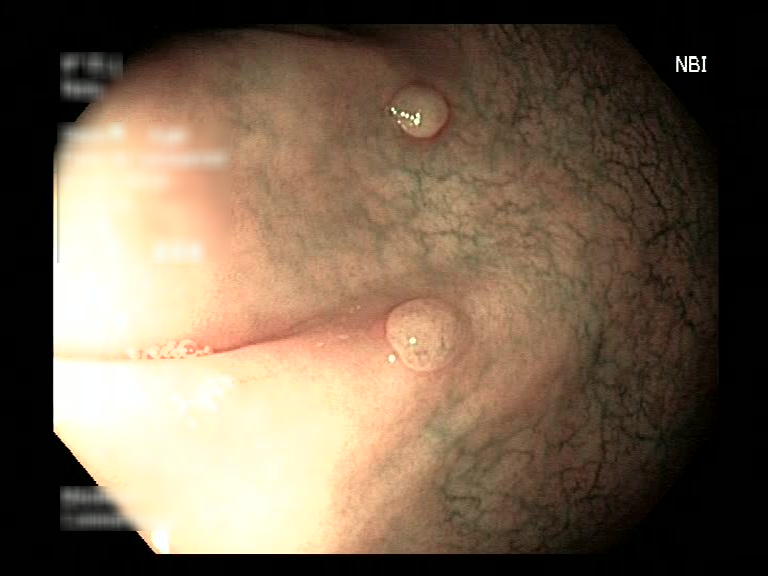

| Lesion | White Light Frame | NBI Frame | White Light Video | NBI Video | Camera Calibration |

| serrated_01 |  |

|

WL.mp4 | NBI.mp4 | cam.xml |